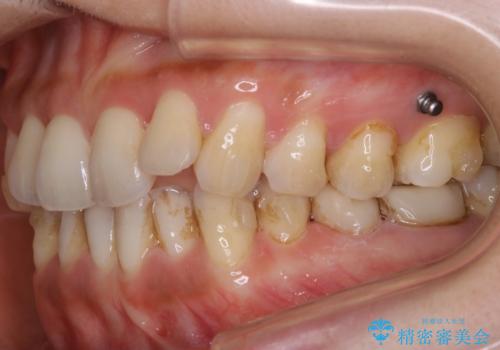

- 歯のガタつきによる見栄えや清掃困難を主訴にご来院されました。

左側の噛み合わせは上の歯が前方に寄ってきてしまっていることが原因のズレがありました。

ガタつき自体は歯列の幅の拡大やディスキング(IPR)でほとんど解消可能でしたが、噛み合わせのズレは歯の移動が必要だったため、左上にマイクロインプラントを使用し噛み合わせの改善とガタつきの解消を同時に進めるという方針をとりました。